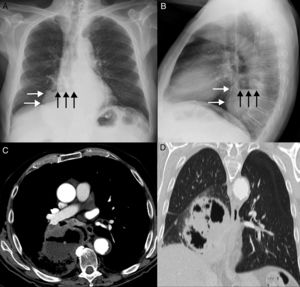

Presentamos el caso de un paciente fumador activo de 73 años sin otros antecedentes de interés que consultó por molestias centrotorácicas y pérdida de peso. Una radiografía de tórax inicial reveló una opacidad retrocardíaca de márgenes bien definidos con un nivel hidroaéreo en su interior, compatible con una hernia de hiato paraesofágica como primera opción diagnóstica, ya que parte del estómago se identificaba en el espacio subfrénico izquierdo (figs. 1A y B). Tres semanas después el paciente consultó por un cuadro autolimitado de hemoptisis; una TC de tórax demostró en ese momento una masa pulmonar extensamente cavitada (figs. 1C y D) con infiltración del mediastino, confirmándose mediante fibrobroncoscopia un carcinoma broncogénico epidermoide.

A) Radiografía posteroanterior de tórax en la que se observa una opacidad en hemitórax derecho (flechas blancas) con un nivel hidroaéreo (flechas negras) en su interior. Nótese la presencia del fundus gástrico (asterisco) en el espacio subfrénico izquierdo. B) Radiografía lateral de tórax en la que se confirma la localización retrocardíaca de la opacidad (flechas blancas) con el nivel hidroaéreo (flechas negras). C) Imagen axial de la TC en la que se identifica una masa extensamente necrótica y cavitada (asterisco) en región paramediastínica del lóbulo inferior derecho. Nótese la presencia de un nivel hidroaéreo en el interior de la cavitación. D) Imagen coronal de la TC (ventana de parénquima pulmonar) en la que se confirma la naturaleza intrapulmonar de la lesión y la integridad de ambos hemidiafragmas.